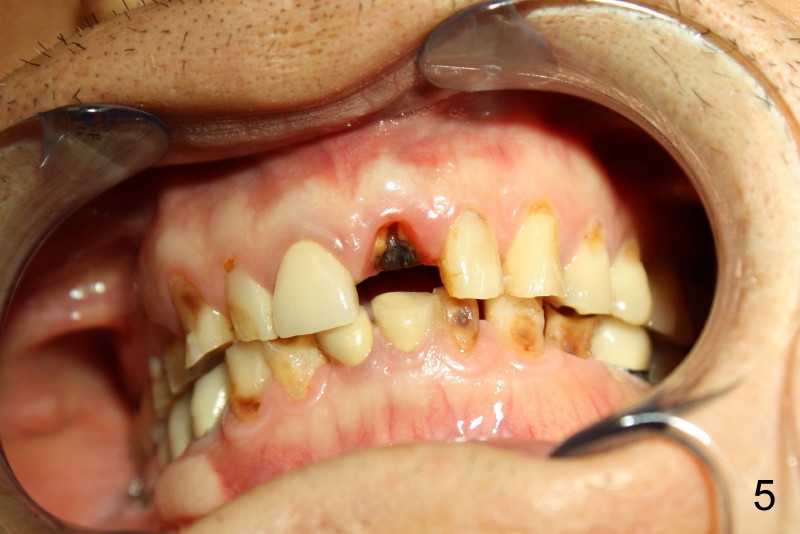

Sixty-five year old man is a bruxer, as shown in Fig.1, 2 (upper. lower arch, respectively, mirror view).  He has a night guard.  Fig.1-3 and Fig.4,5 are taken before and after crown fracture of the tooth #9, respectively.  It appears that the tooth is nonsalvageable.

Although gutta percha of #9 is overfilled, there is no active infection (Fig.3,4).  Can we place an implant immediately after extraction without loading or minimal loading?